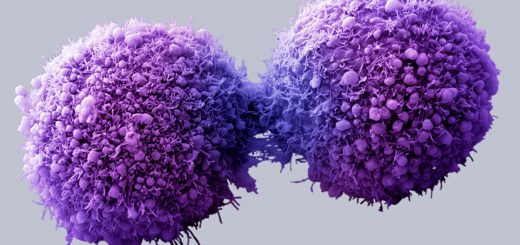

کپسایسین چرخهی زندگی سلولهای سرطانی را با بهبود دادن مرگ برنامهریزی شدهی سلولها تحت تاثیر قرار میدهد. این مکانیسم معمولاً در سلولهای سرطانی به صورت عادی انجام نمیشود، بلکه این سلولها زنده میمانند و تکثیر میشوند. با این حال، شواهدی وجود دارند که نشان میدهند کپسایسین میتواند برخی از سلولهای سرطانی را از بین ببرد.